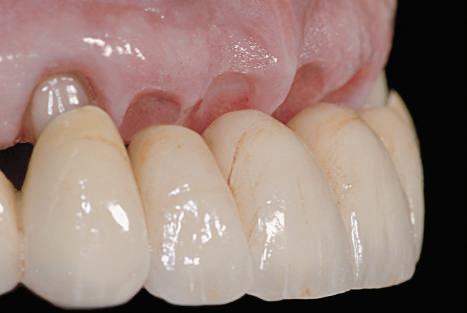

Figurile 3, 4. Întrucât poziţia implantului era mezială faţă de ideal, bonturile individualizate s-au conceput plate pe profilul mezial, dar au prezentat provocări în privinţa conturării restauratoare. 5. Restaurările implantare de la nivelul 1.2. şi 2.2. susţin o FPD metalo-ceramică cimentată între incisivii laterali.

Pentru înlocuirea dintelui anterior, selectarea materialului este importantă în succesul estetic, gradul de afişare a dintelui şi gingiei în timpul surâsului având pondere importantă în decizie. S-a demonstrat că în funcţie de grosimea ţesutului care se află deasupra bontului, unul din titan poate crea umbră prin ţesuturile moi. Când grosimea ţesutului era mai mică de 2mm, autorii au arătat că ochiul uman putea detecta reflecţia luminii de pe bontul de titan. Astfel, orice implant plasat vestibular de dinţii adiacenţi sau cu mai puţin de 3mm sub marginea gingivală finală anticipată la un pacient care afişează treimea cervicală a dinţilor în timpul zâmbirii poate necesita un bont de zirconiu. Acest lucru va minimiza umbra situată apical de marginea gingivală, observată în cazul bonturilor de titan. Pacienţii care nu afişează treimea cervicală a dinţilor în cursul zâmbetului larg, permit o mai mare flexibilitate în privinţa alegerii materialului, pentru că riscul reflecţiei date de afişarea metalului este minimă (fig. 11-13). Bonturile de zirconiu reprezintă o opţiune excelentă atunci când accesibilitatea la marginile restaurative este îndoielnică, deoarece permit ca marginile restaurării să fie mai apropiate de marginea gingivală finală, în special în cazurile în care se anticipează recesie gingivală. Dacă există orice retracţie ulterioară, joncţiunea dintre dinte şi restaurare este mai puţin vizibilă şi există o mai mică probabilitate pentru afişarea umbrei în cazul unui bont metalic.

şi pentru a corecta lungimea vizuală a restaurării. Aceasta se poate obţine prin ajustarea nivelului gingival şi a profilului ţesutului moale pe modelul de ţesut moale şi prin fabricarea bontului în conformitate cu acest profil modificat. Totuşi, dacă implantul nu s-a poziţionat la o adâncime de 3-5mm în raport cu marginea gingivală, modificarea nu este posibilă (fig. 11-13).